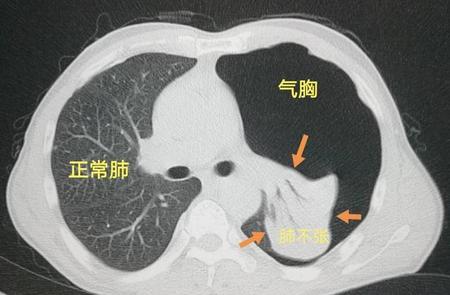

肺不张多久肺会坏死(肺泡坏死是什么病)

肺不张分两种情况:压迫性肺不张和阻塞性肺不张。不管哪种情况,只要血管(肺动脉和支气管动脉)没有破坏,一般就不会发生坏死。

关于压迫性肺不张当气胸、胸腔积液等原因,胸膜腔压力...